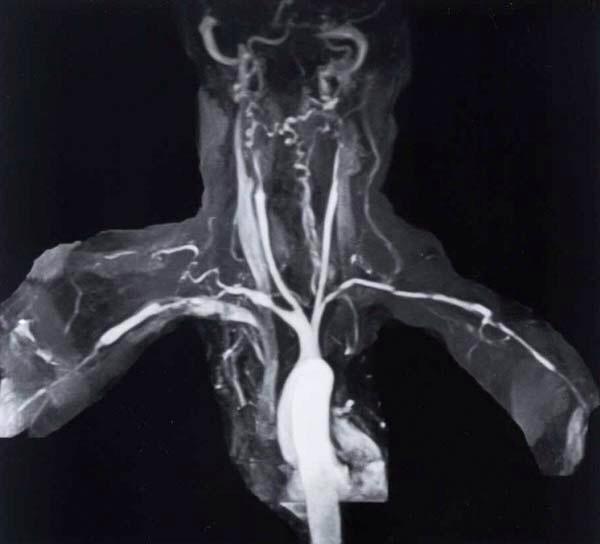

Takayasu Arteriitis Deutschland - Bist Du auch betroffen??

Seid Ihr auch an dieser Nadel im Heuhaufen erkrankt?

Ich würde gerne Erfahrungen austauschen und Eure Geschichten hören - vermutlich ist bei Euch auch viel passiert bis Ihr Euren 'Takayasu' gefunden habt!?